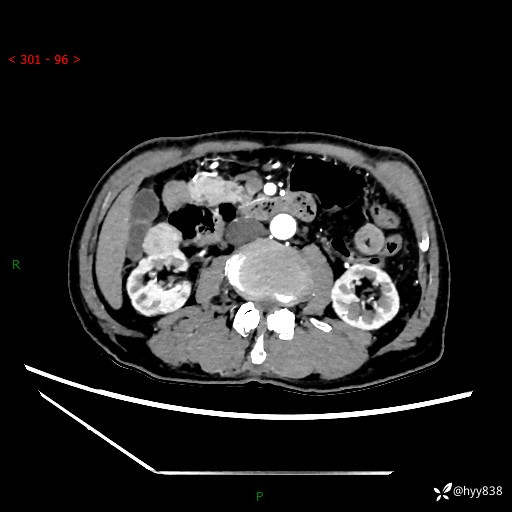

辅助检查:CT

临床诊断:肾肿物

肾脏CT平扫

增强(皮质期+髓质期+排泄期)

三期CT值:132hu 107hu 81hu